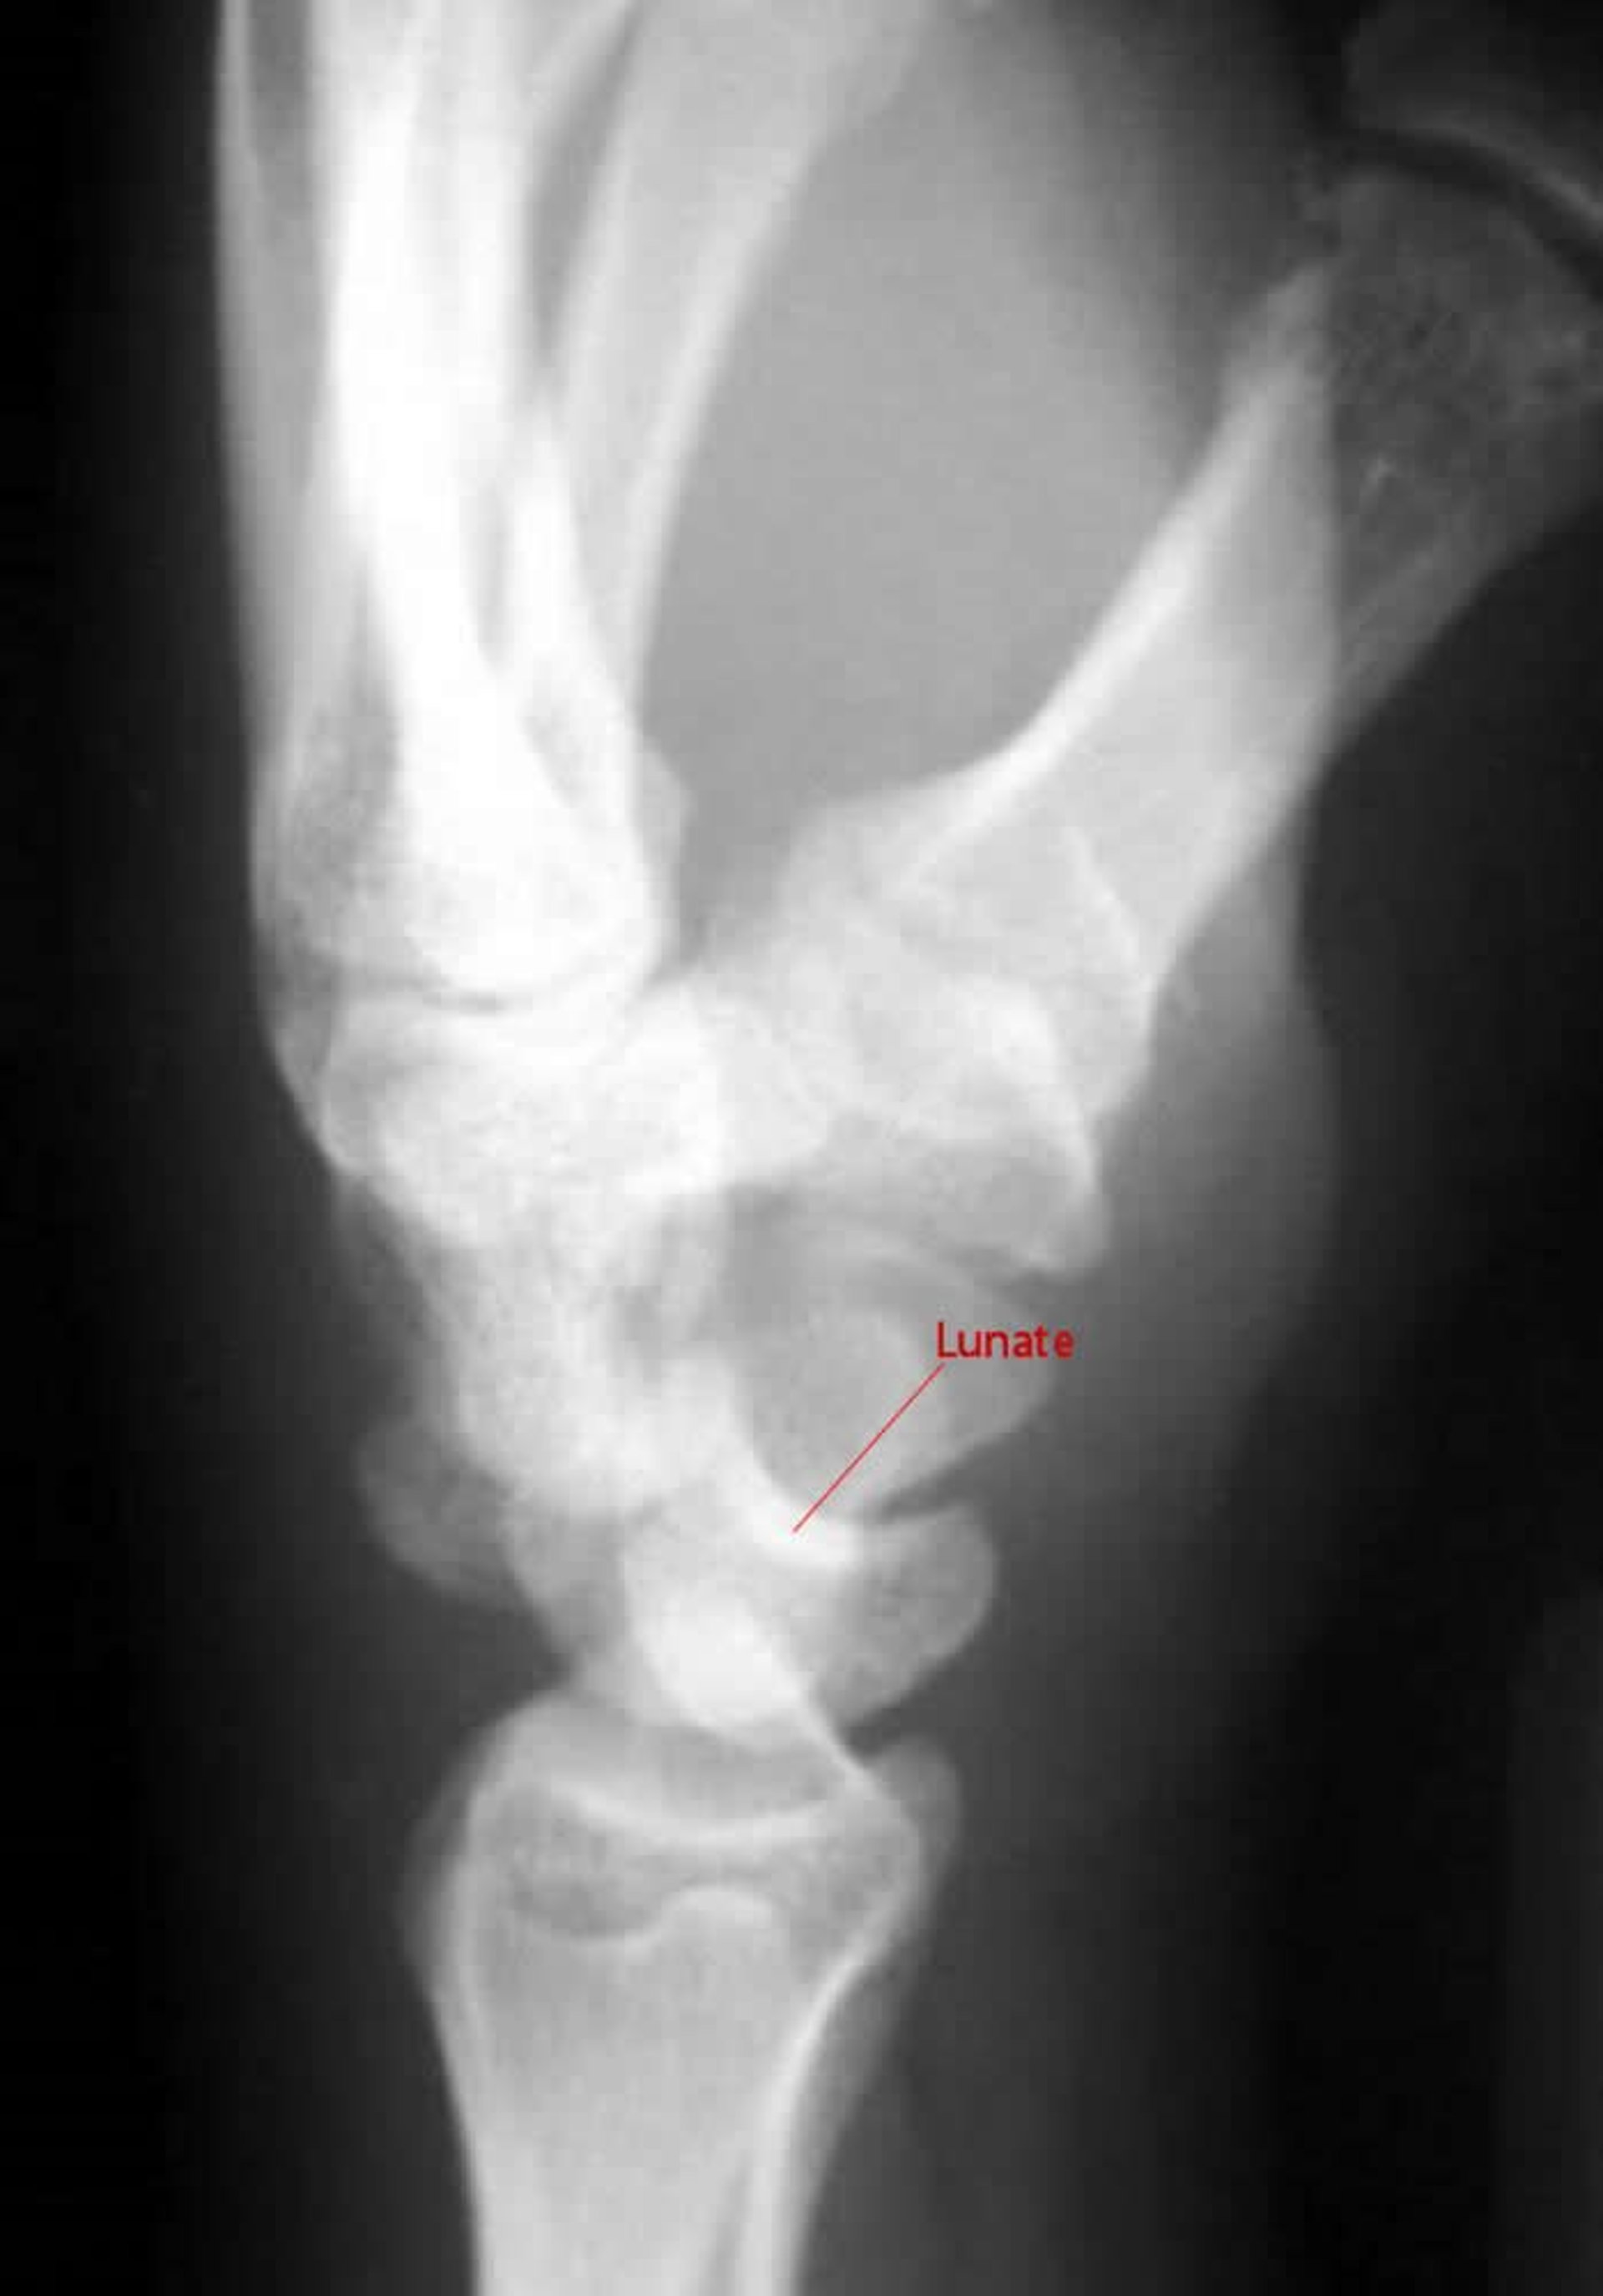

Perilunäre Luxation

In der Seitenansicht einer Perilunatum-Luxation bildet das Capitatum keinen Gelenkpunkt mit dem Lunatum.